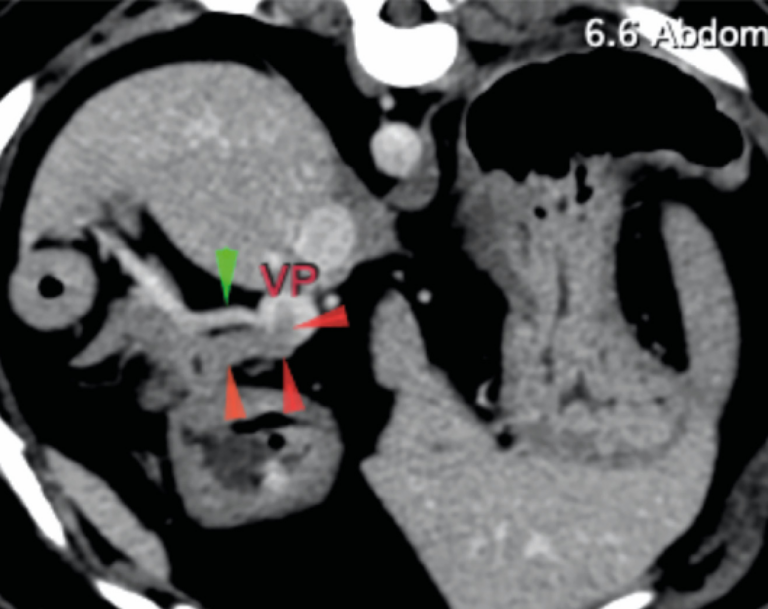

- Intervencionismo en la válvula pulmonar en perros: revisión de técnicas y resultados.